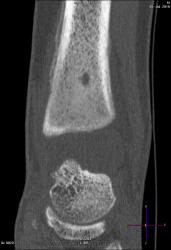

Молодой человек 18 лет поступил в стационар с ноющими периодическими болями в правом г/стопном суставе, год назад, в августе была травма(во время тренировки), по снимку без костно-травматических изменений, а вот снимок проведенный 28.06.10г.:

Вчера было проведено КТ-г/стопного сустава:

Только по рентгенограммам (без учета КТ) высказался-бы в пользу абсцесса Броди.